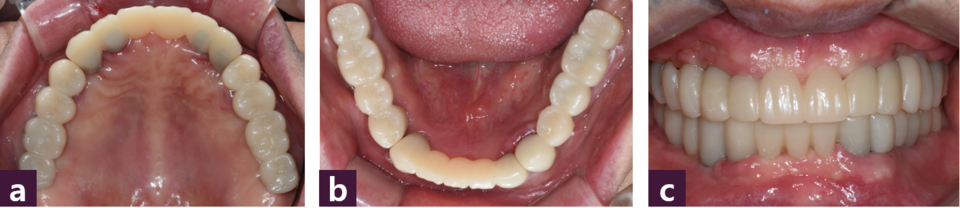

작업 모형을 제작한 후 상하 작업 모형을 반조절성 교합기에 마운팅하여 맞춤형 지 대주(titanium customized abutment)와 상하악 모두 전치부와 양측 구치부로 3분획한 PMMA 임시치아를 제작하였다 [그림 7].

시멘트유지형 PMMA 임시 치아를 tempbond 임시 시멘트로 접착하였다 [그림 9].